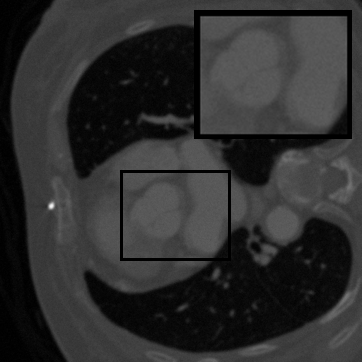

Figure 3: Visual comparison on TomoBank and LoDoPaB under random masking (ratio = 0.8). Rows 1 and 3 show the inpainted sinograms, while Rows 2 and 4 present the corresponding FBP (Ramachandran and Lakshminarayanan, 1971)-reconstructed images.

Table 1 summarizes the quantitative performance of FCDM and all baselines on the TomoBank and LoDoPaB datasets under both random and periodic masks. Figure 3 presents qualitative comparisons at a mask ratio of 0.8, showing both the inpainted sinograms and the reconstructed images obtained using FBP (Ramachandran and Lakshminarayanan, 1971). Across all settings, FCDM consistently achieves the highest SSIM and PSNR values, demonstrating its strong capability in recovering structural details and suppressing noise-induced artifacts. Visual results in Figure 3 further confirm that FCDM produces smoother and more consistent sinograms, while other methods often exhibit angular streaking or local inconsistencies.